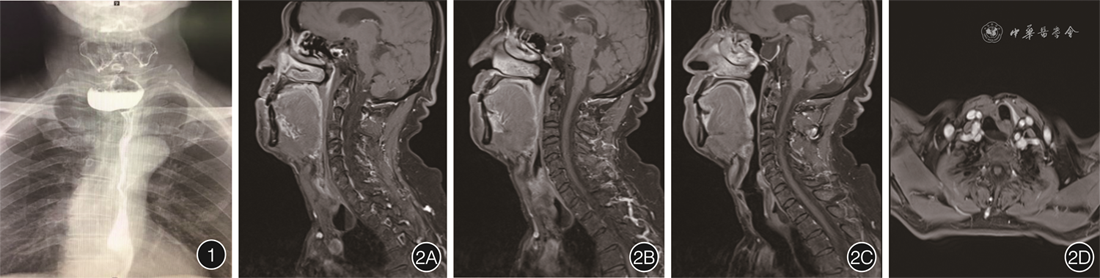

患者男,62岁,因“上腹部疼痛,进食后呛咳1月余”收治入院。患者吞咽困难、声音嘶哑、口气,伴咳嗽、气短,自诉平时进食伴吞咽不畅、吞咽疼痛,入睡后颈部有气泡声,说话时有突然失音。吞咽困难评分为3分(0分,可正常饮食;1分,能进食部分固体食物;2分,只能进食半流质;3 分,只能进食流质;4分,无法进食)。入院前行钡剂造影检查显示食管上端偏右侧壁见囊袋状存钡影,直径约4.9 cm,余食管各段及贲门未见明显异常,诊断为Zenker憩室(图1),颈部磁共振平扫+增强检查示食管上段憩室(图2)。拟行内镜下憩室内黏膜剥离术联合金属夹封闭术治疗。患者在术前1周停用抗凝药物和抗血小板聚集药物,具体手术过程(图3、视频)如下:(1)在完成气管插管和麻醉后,用Dual刀在距门齿16 cm处的憩室口进行内镜标记。(2)黏膜下注射生理盐水、亚甲蓝和肾上腺素混合物抬高憩室内黏膜。(3)黏膜切开刀沿标记点将憩室内部黏膜预切开并行黏膜下剥离,该患者剥离至憩室底部时,黏膜下层粘连明显,局部黏膜下层提升不良,在此处紧贴固有肌层进行剥离,剥离完成后无明确穿孔。(4)黏膜下剥离完成后,用金属夹封闭憩室开口,修复食管壁肌层。(5)内镜下放置胃管,结束手术。术后立即给予抗感染(头孢哌酮钠舒巴坦钠)、鼻饲营养支持、抑酸补液等处理。术后患者无明显疼痛和发热,自诉颈部异响、口气、声音嘶哑、进食困难、咳嗽、气短等症状消失,于术后第三天带胃管出院。半月后患者复查钡剂造影示憩室腔完全闭合(图4),拔除胃管,逐步过渡至正常饮食。术后3月余复查胃镜(图5)示憩室腔消失,吞咽困难评分为0分。随访至2023年4月30日,患者无不适。